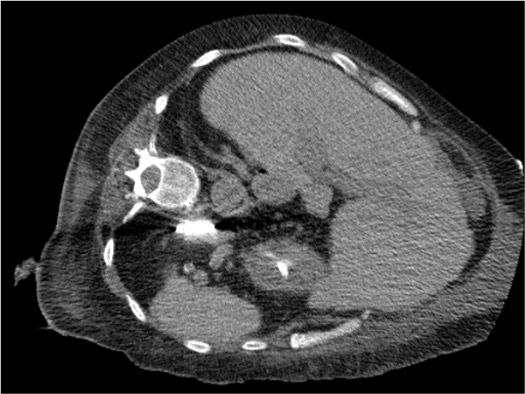

Right Adrenal

- Located posterior to the IVC, between the liver and right kidney, superior to the right renal hilum

- Shape: "Y-shaped" or triangular on CT; medial limb abuts IVC posterolateral wall

- Proximity hazards: IVC (medial), right renal vein (inferior), duodenum (anterior/inferior), liver (anterior)

- Posterior approach: between 12th rib and iliac crest, aim medial to right kidney; avoid pleural reflection superiorly

Right Adrenal — CT Approach

- Posterior approach: skin entry between 12th rib and iliac crest, lateral paraspinal musculature

- Aim medial to right kidney; trajectory directed toward adrenal limb harboring the lesion

- Avoid IVC and right renal vein (medial and inferior boundaries); confirm safe distance on axial planning CT

- Superior approach: risk of pleural transgression if above 12th rib — confirm pleural reflection on coronal scout

- Duodenum risk (anterior/inferior to right adrenal) — hydrodissection mandatory if <1 cm clearance